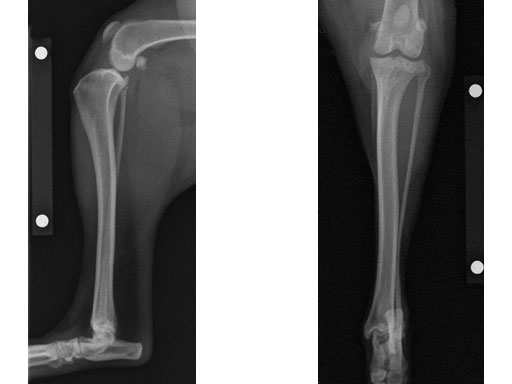

Case 1: Two-year-old Labrador Retriever

2-years-old Labrador Retriever, 30 kg, female. Chronic lameness in both hind limbs, chronic bilateral cranial cruciate ligament tears, with subsequent stifle joint instability and degenerative joint disease. At that time, she was more clinically lame on the left hind limb, and a surgical correction was subsequently performed on this limb. X-rays of the stifle joint revealed the degenerative joint changes and an effusion; the tibial plateau slope was 20. In addition, the x-rays confirmed that there was a slight amount of tibial torsion that also was observed clinically, accounting for a slight internal rotation of the distal limb. Radiographically, this could be assessed by a 4 mm shift of the normal point of intersection of the medial aspect of the calcaneus with the deepest point of the talar sulcus.